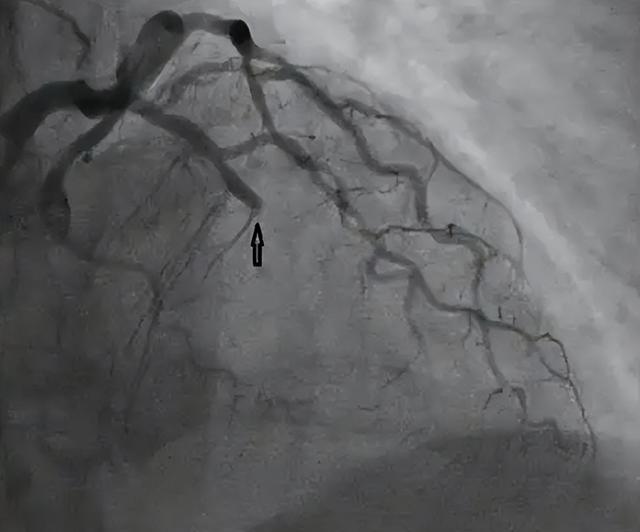

有信息网友从报道的视频中发现,男子的裤子上有出现尿失禁的情况,借此认为其所患上的疾病是心梗,这也是多数网友所认为的致死原因。

的确,男子患心梗的可能性并不算小,有些人认为心梗属于“老年病”,中年、青年群体并不会患上,事实则并非如此,像那些长期处于疲惫状态的人群哪怕年轻的也可能患上心梗。

年轻人发生心梗是有很大猝死风险的,根据我国卫健委发布数据显示,我国每年突发急性心梗的人数要有100万人左右,其中每3个患者中就会有1人死亡,死亡率超3成,是我们必须要重视的一类疾病。

无论最终公布的疾病情况是否真为心梗,当代人都有必要注重心梗问题,了解心梗诱因,察觉心梗症状,如何正确应对突发心梗都是我们需要了解的。